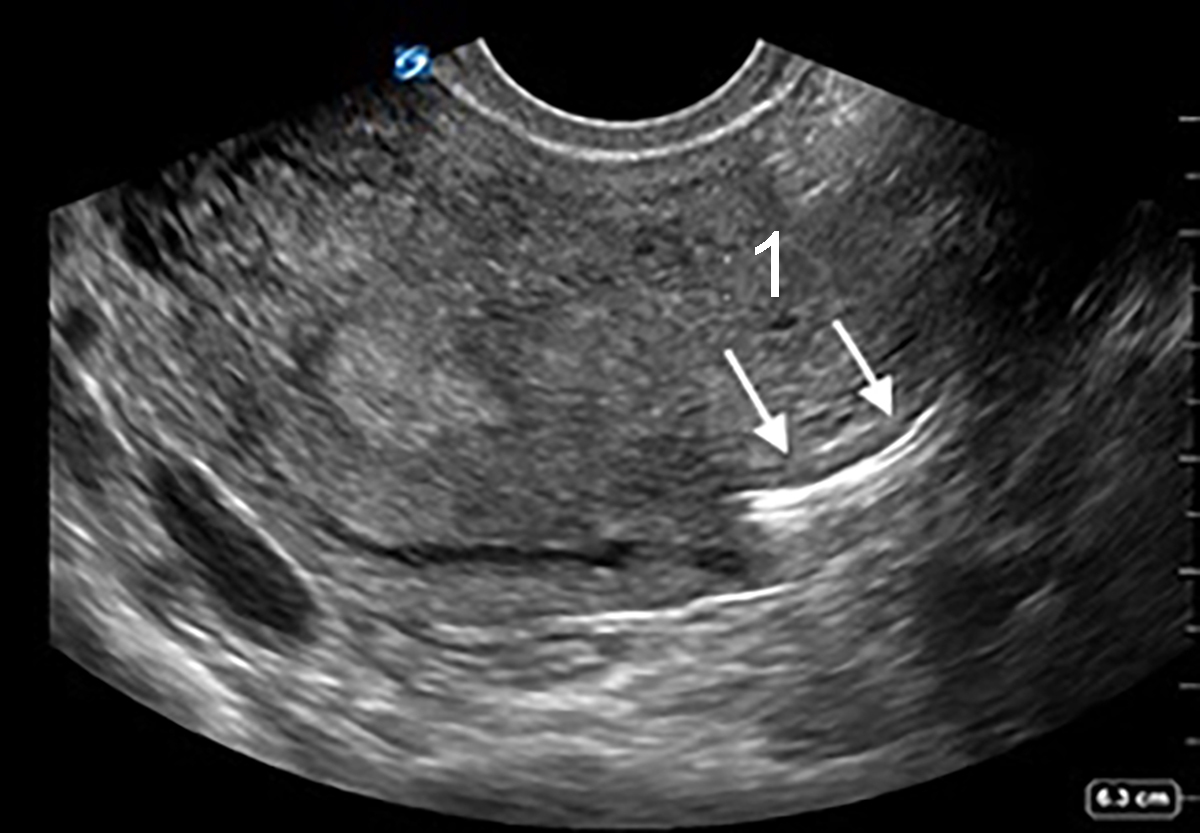

移行する子宮内避妊器具 (IUD) の横断像で骨盤膣 (テレビ) 子宮

IUD